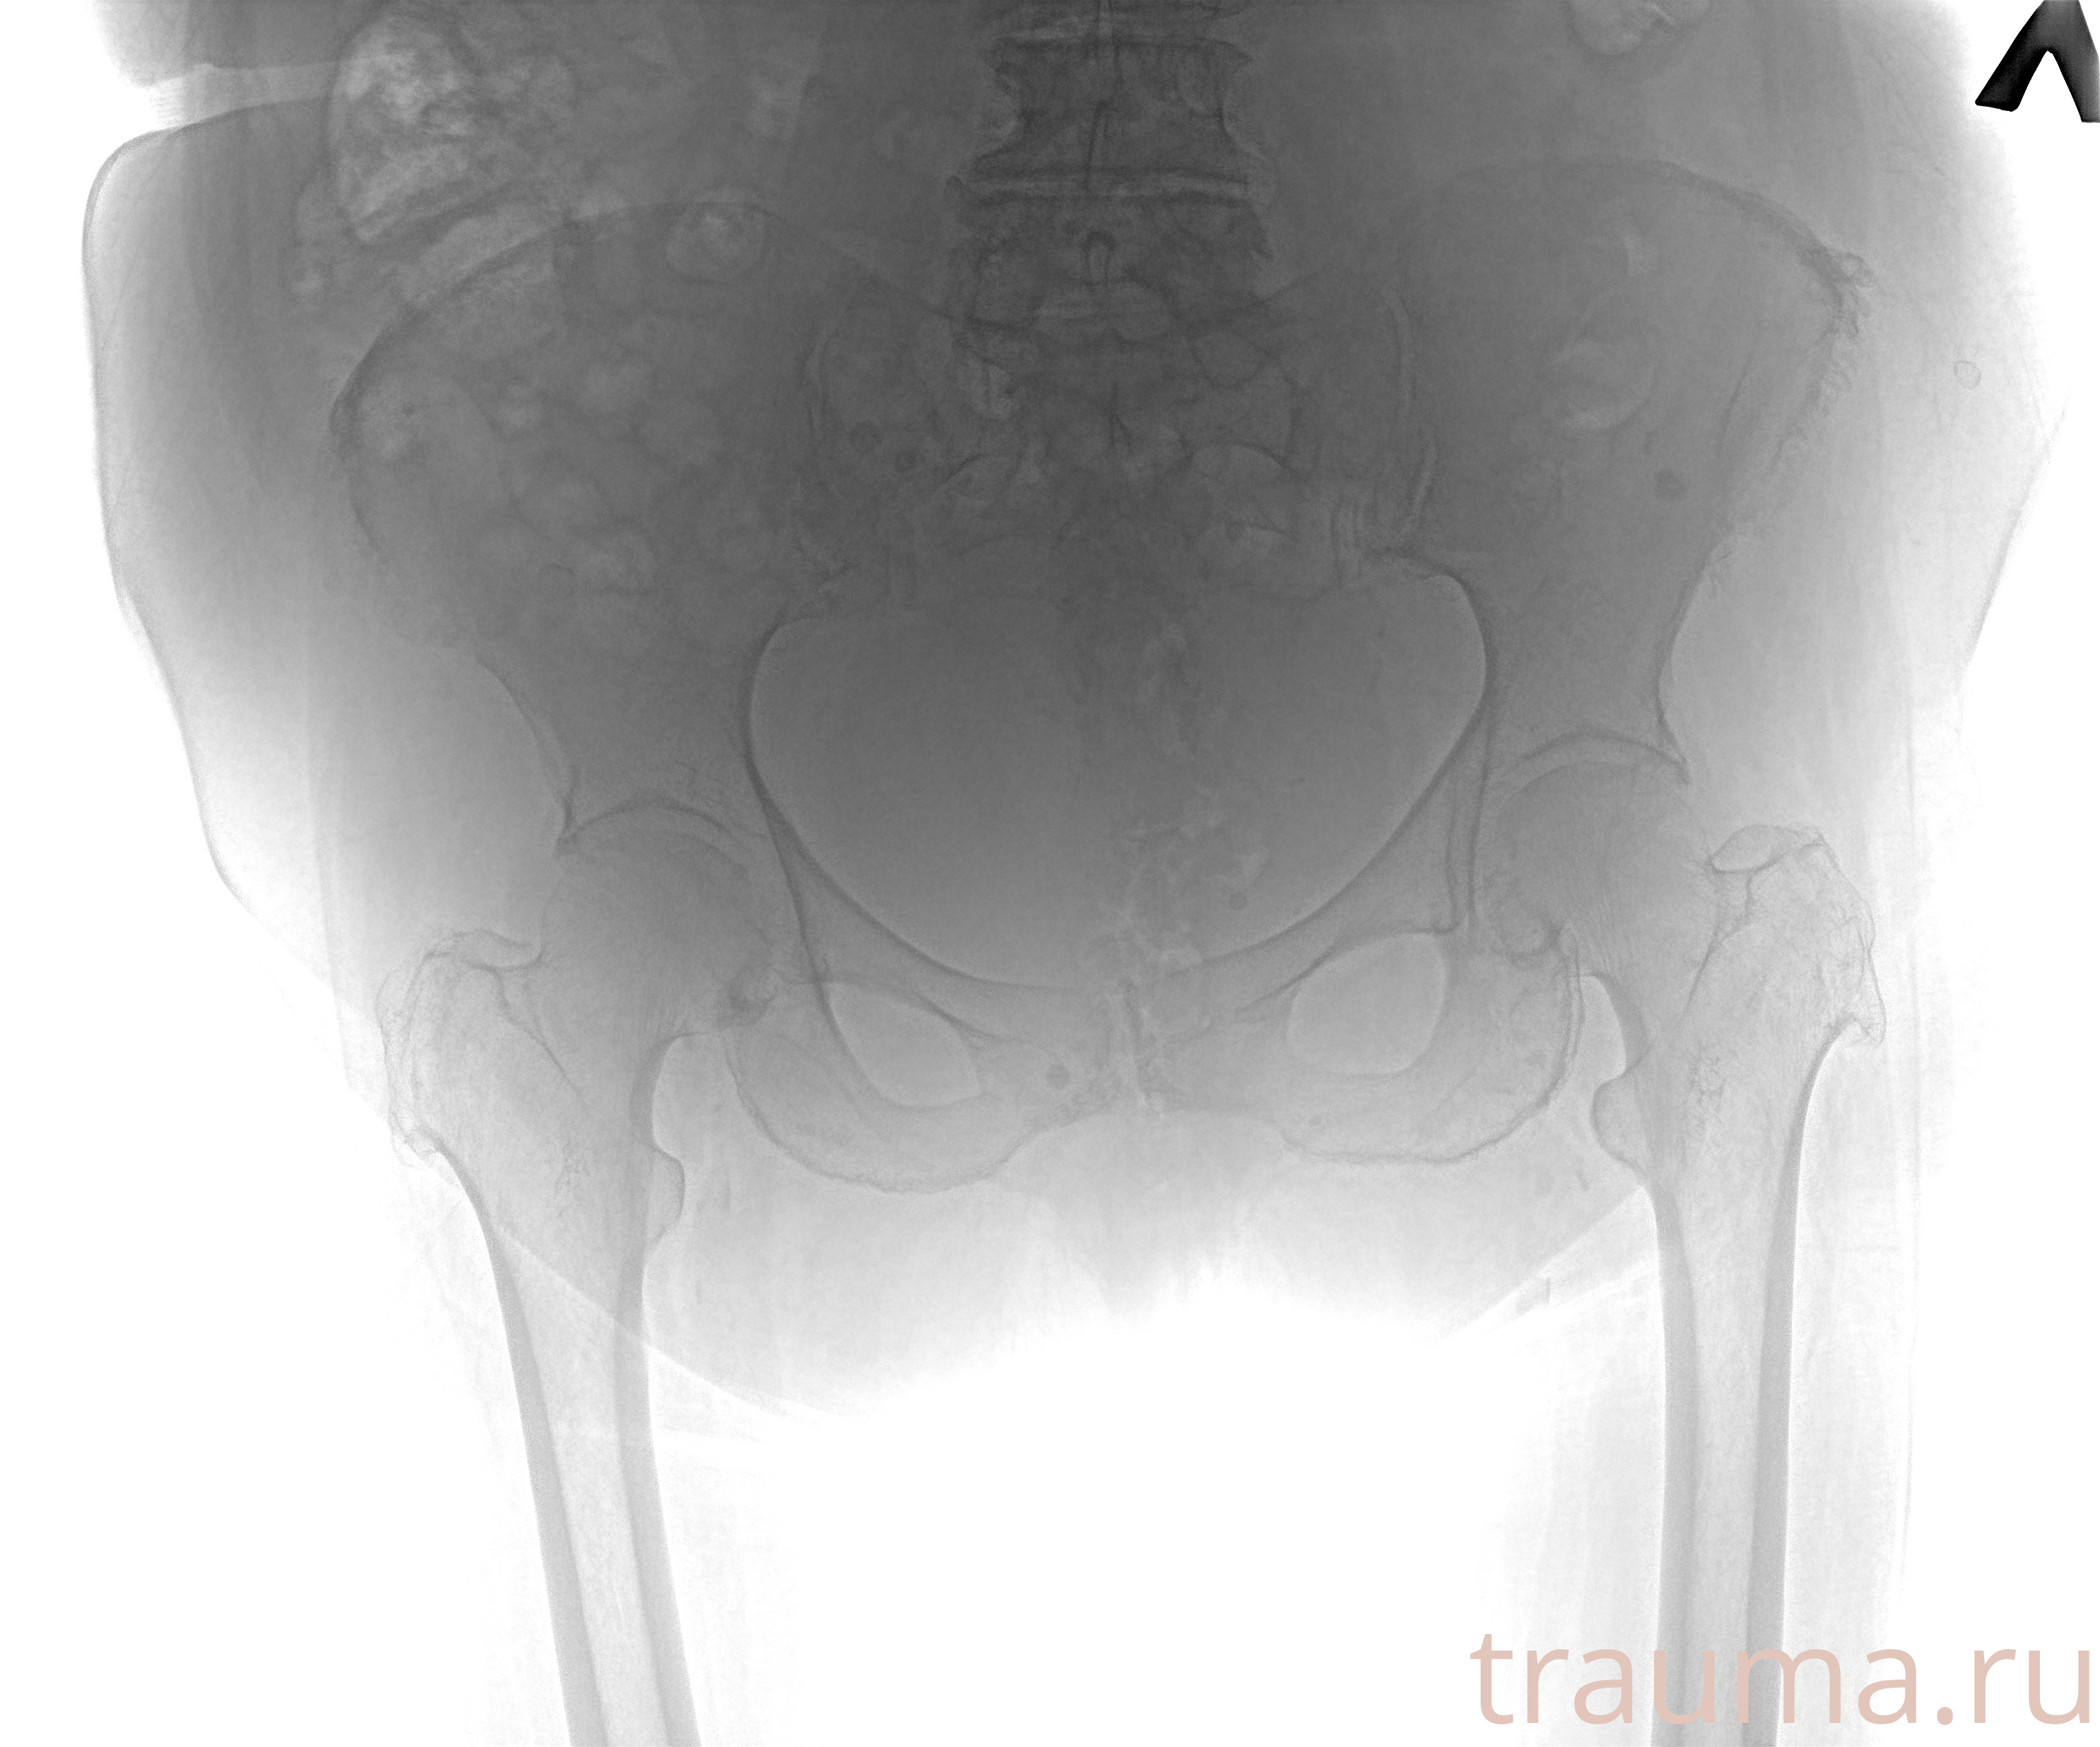

Рентгенограммы

Рентген на дому: по вашему адресу приезжает врач-рентгенолог, травматолог-ортопед с мобильным рентгеновским аппаратом, проводит диагностику травмы или заболевания, делает необходимые рентгенограммы, дает рекомендации по дальнейшему лечению. Получить качественные снимки в домашних условиях возможно благодаря уникальной методике, разработанной МосРентген Центром для института  Склифосовского